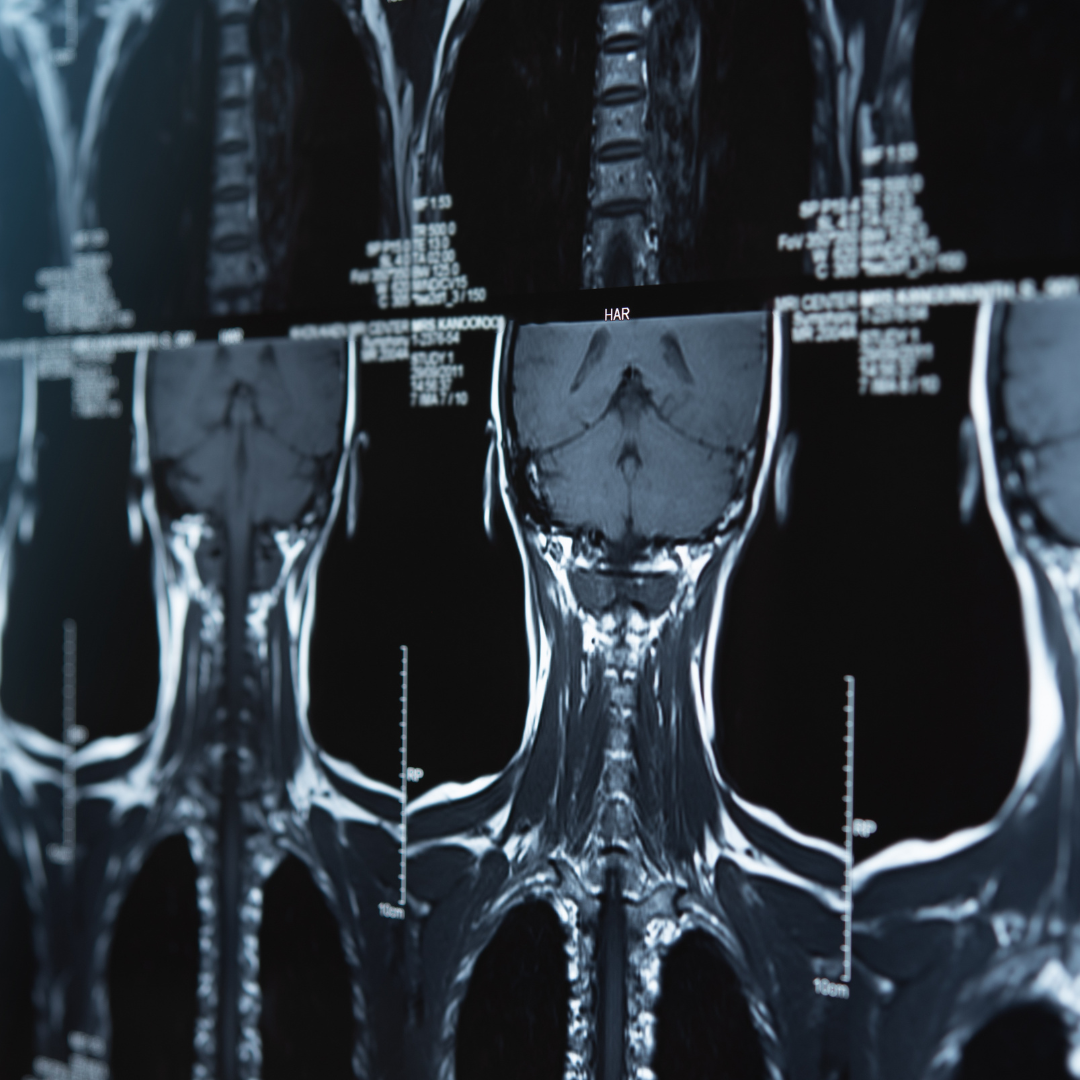

Interpretarea imagisticii coloanei vertebrale și corelarea clinică

Un curs practic care te învață cum să interpretezi RMN-ul, CT-ul și radiografiile coloanei vertebrale și cum să corelezi imaginile cu tabloul clinic al pacientului.

Lecția 1 – Anatomia coloanei vertebrale pe RMN: orientare și recunoaștere

Lecția 2 – De la RMN la pacient: când modificarea explică simptomul

cum se interpretează corect RMN-ul coloanei vertebrale

cum corelezi imaginile cu simptomatologia pacientului